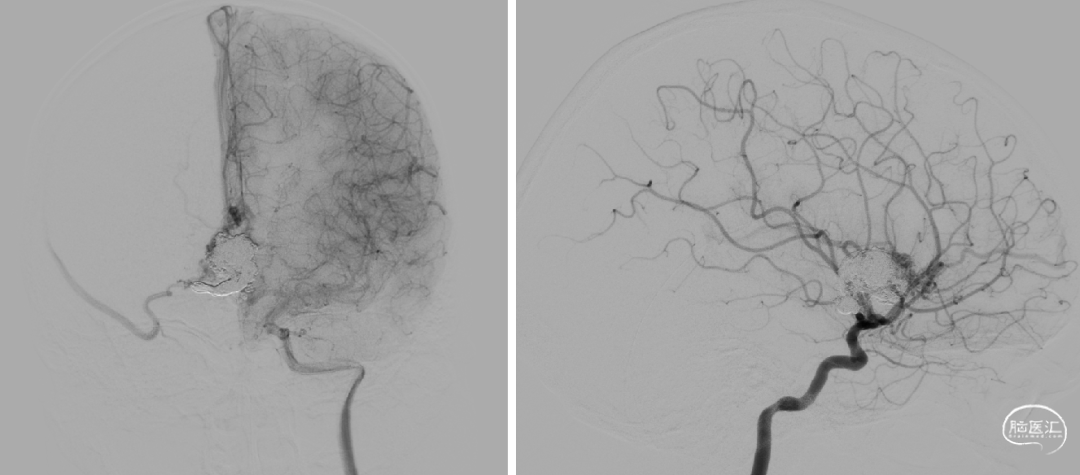

术前检查

🔹治疗方案:全麻下经静脉入路脑动静脉畸形栓塞术